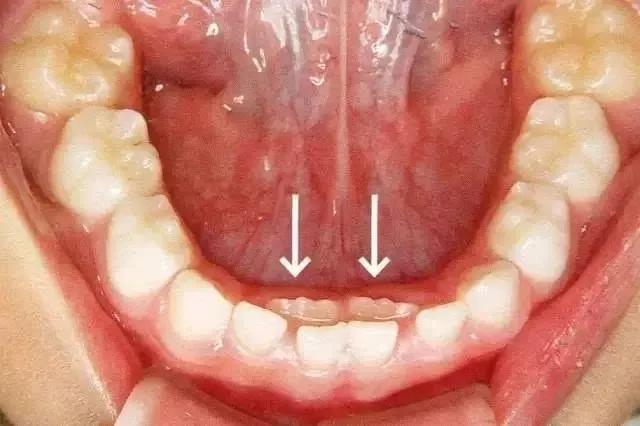

这种孩子乳牙还没脱落,新牙就长出来的现象,就是所谓的“双排牙”现象。也就是医生常说的“乳牙滞留”。

箭头所指为恒牙